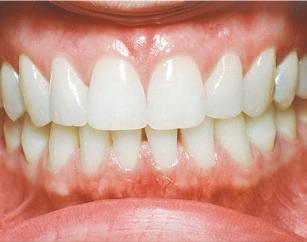

How healthy is your smile?

Stage IV –Severe Periodontitis